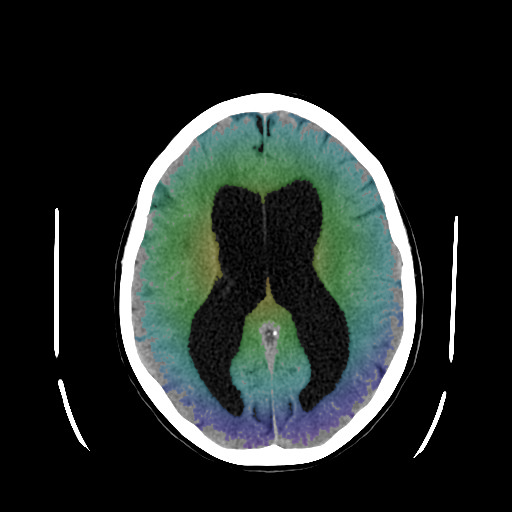

Αξονική τομογραφία ασθενούς με υδροκέφαλο αριστερά, με διάταση του κοιλιακού συστήματος (κόκκινο περίγραμμα). Σύγκριση με φυσιολογικό κοιλιακό σύστημα δεξιά (πράσινο περίγραμμα). |